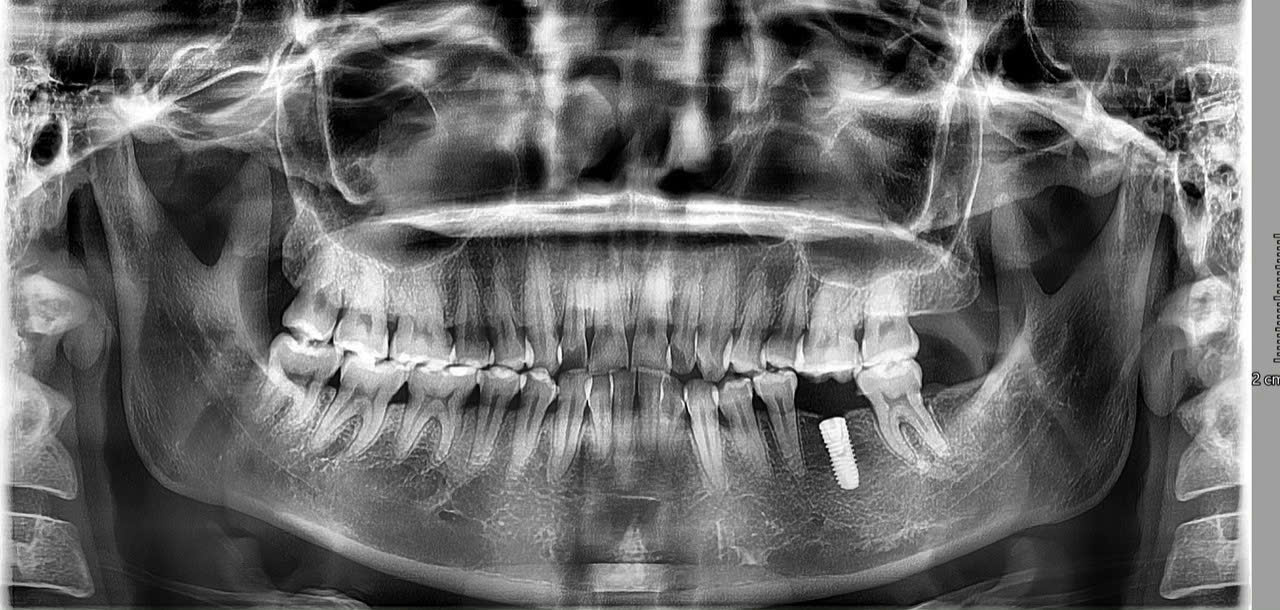

Hình 1: Implant có tuổi thọ rất cao và hoàn toàn có thể sử dụng trọn đời

Trồng răng Implant hiện đang là lựa chọn hàng đầu cho người mất răng nhờ độ bền vượt trội, khả năng ăn nhai chắc chắn và tính thẩm mỹ tự nhiên. Một trong những câu hỏi được quan tâm nhất là: “Implant có thể dùng cả đời không?” Đây là vấn đề nhiều người tìm hiểu trước khi quyết định phục hình răng bằng phương pháp này.

Thực tế, răng Implant có tuổi thọ rất cao và hoàn toàn có thể sử dụng trọn đời nếu được đặt đúng kỹ thuật và chăm sóc đúng cách. Bài viết dưới đây sẽ giải thích chi tiết về tuổi thọ Implant, những yếu tố tác động và các bí quyết giúp Implant bền vững theo thời gian.